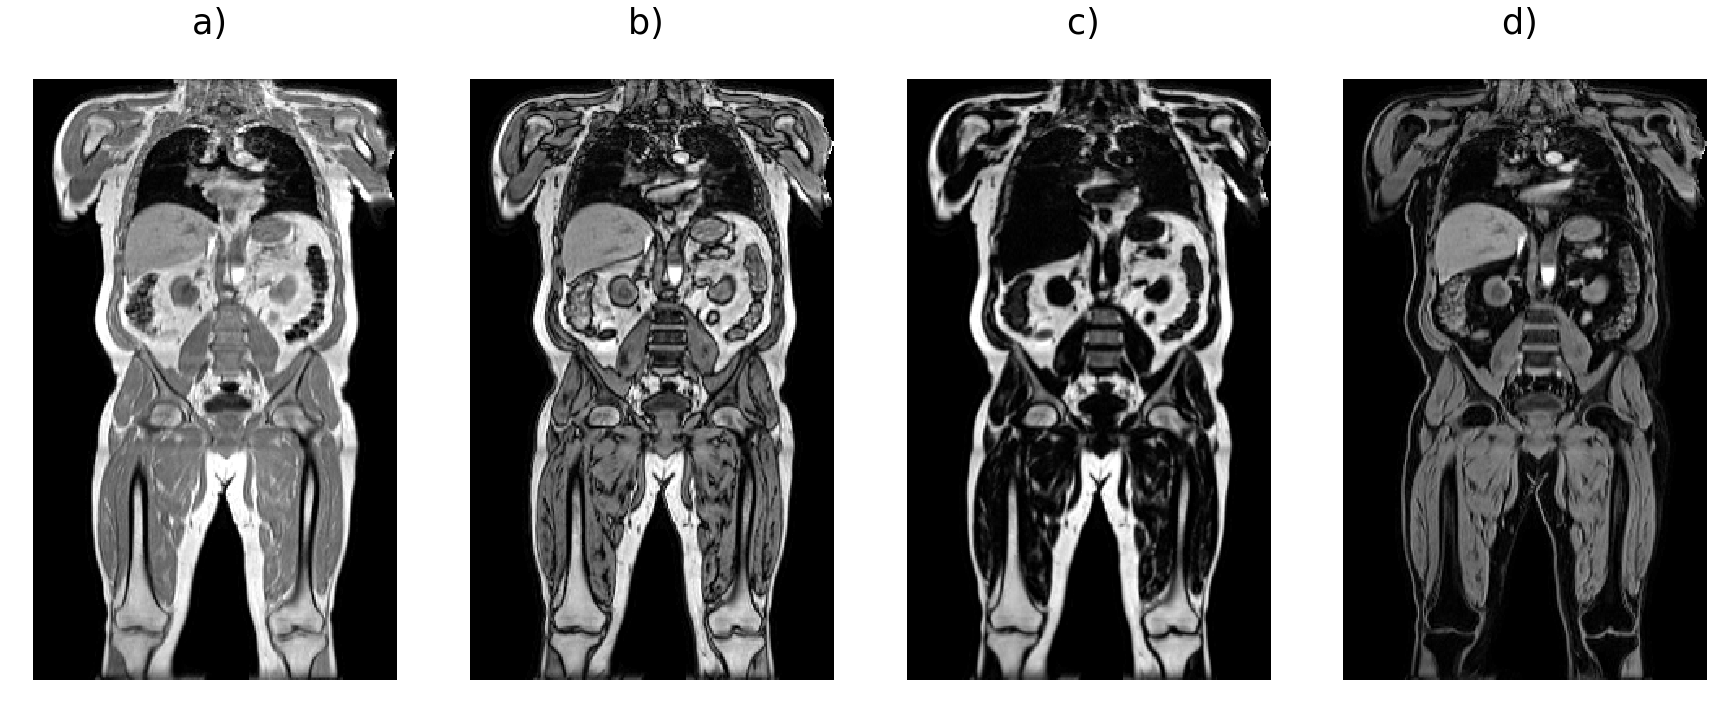

For the training data, fat-water separation was performed by the scanner reconstruction software on each Dixon series as provided by the UK Biobank. We performed minor preprocessing to assemble the six series into a single volume for each channel [6] (Fig. 1 a-d). Briefly, the six series were resampled to the same resolution (), bias-field correction [40] was performed on the in-phase volume and the estimated bias field applied to the other channels for each series, resulting in a final volume of size . Bias-field correction was performed a second time on the blended in-phase volume and the estimated bias field was applied to the other channels. Estimating the bias-field is a particularly computationally expensive step, the entire process takes approximately 20 minutes per scan. We selected 1,027 participants as swap-free ground truth data for our experiments, where visual inspection of the fat and water channels was performed for each participant to ensure no substantial swaps were present. The participants were chosen to cover a broad range of age, gender and body mass index values. During the process of quality control, we also identified more than 70 participants with at least one fat-water swap in the original fat and water channels. We used those scans to verify swap correction by visual inspection. When developing the neural network model we used the and channels as our input data and the and channels as the training labels.

There are indeed a variety of more complex fat-water swaps in the UK Biobank Dixon MRI datasets, including partial swaps that cover only a fraction of the volume or swaps related to the multiple (six) series acquired in the UK Biobank abdominal protocol. For example, the top of the liver may be swapped when it appears in the second series and is isolated from all other tissue by the lungs (Fig. 1 e-f), or one of the abdominal muscles may be swapped when isolated from all other tissue by internal fat. Localised fat-water swaps may also occur due to field inhomogeneities at the boundary of the field of view (Fig. 1 k-l). Swaps occur more frequently in subjects of extreme sizes, therefore not being able to quantify or even completely discarding these subjects may introduce bias in population studies. The UK Biobank is currently acquiring images for 100,000 participants, and plans to scan as many of them as possible for a second time as well as performing a separate COVID-19 study. This means that substantially more than 100,000 scans will be performed, thus we estimate that the images from close to 10,000 participants could be affected. It is essential that we develop methodologies that will ensure minimal data waste and that all analyses resulting from this impressive collection will reach their full potential.